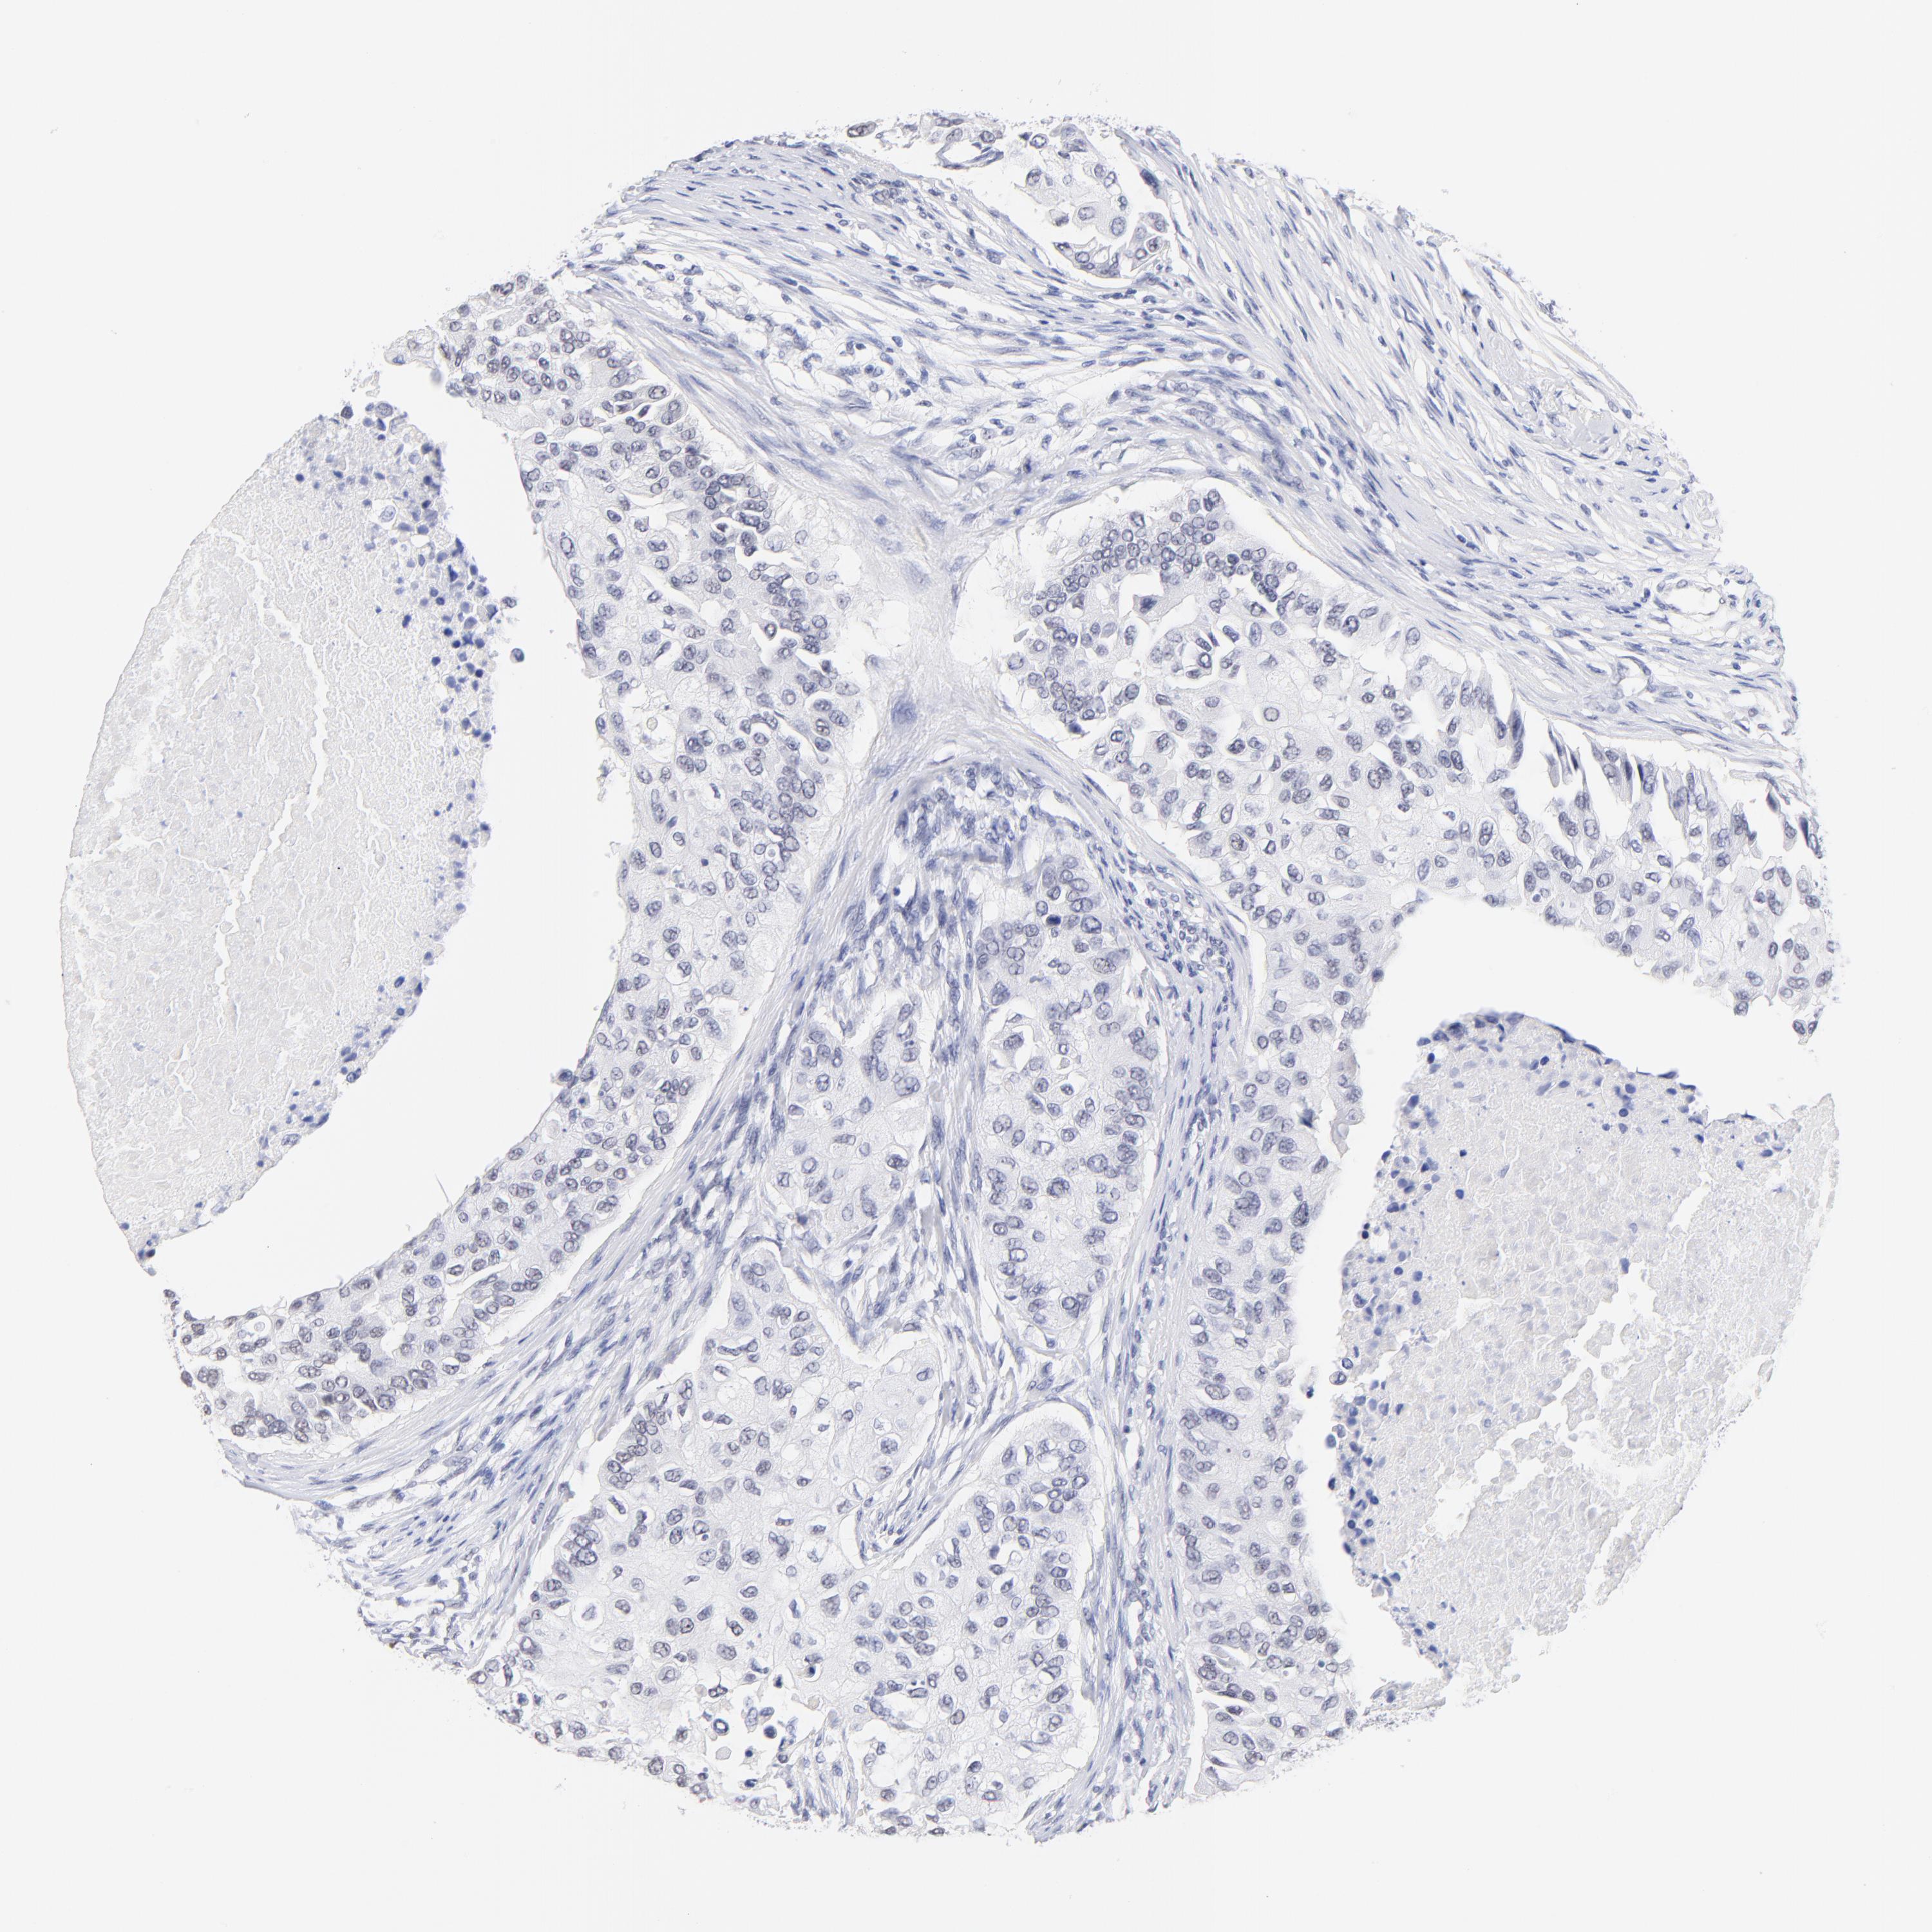

BRCA TCGA BRCA VALIDATION PROTEIN EXPRESSION

ANTIBODIES

AND

VALIDATION